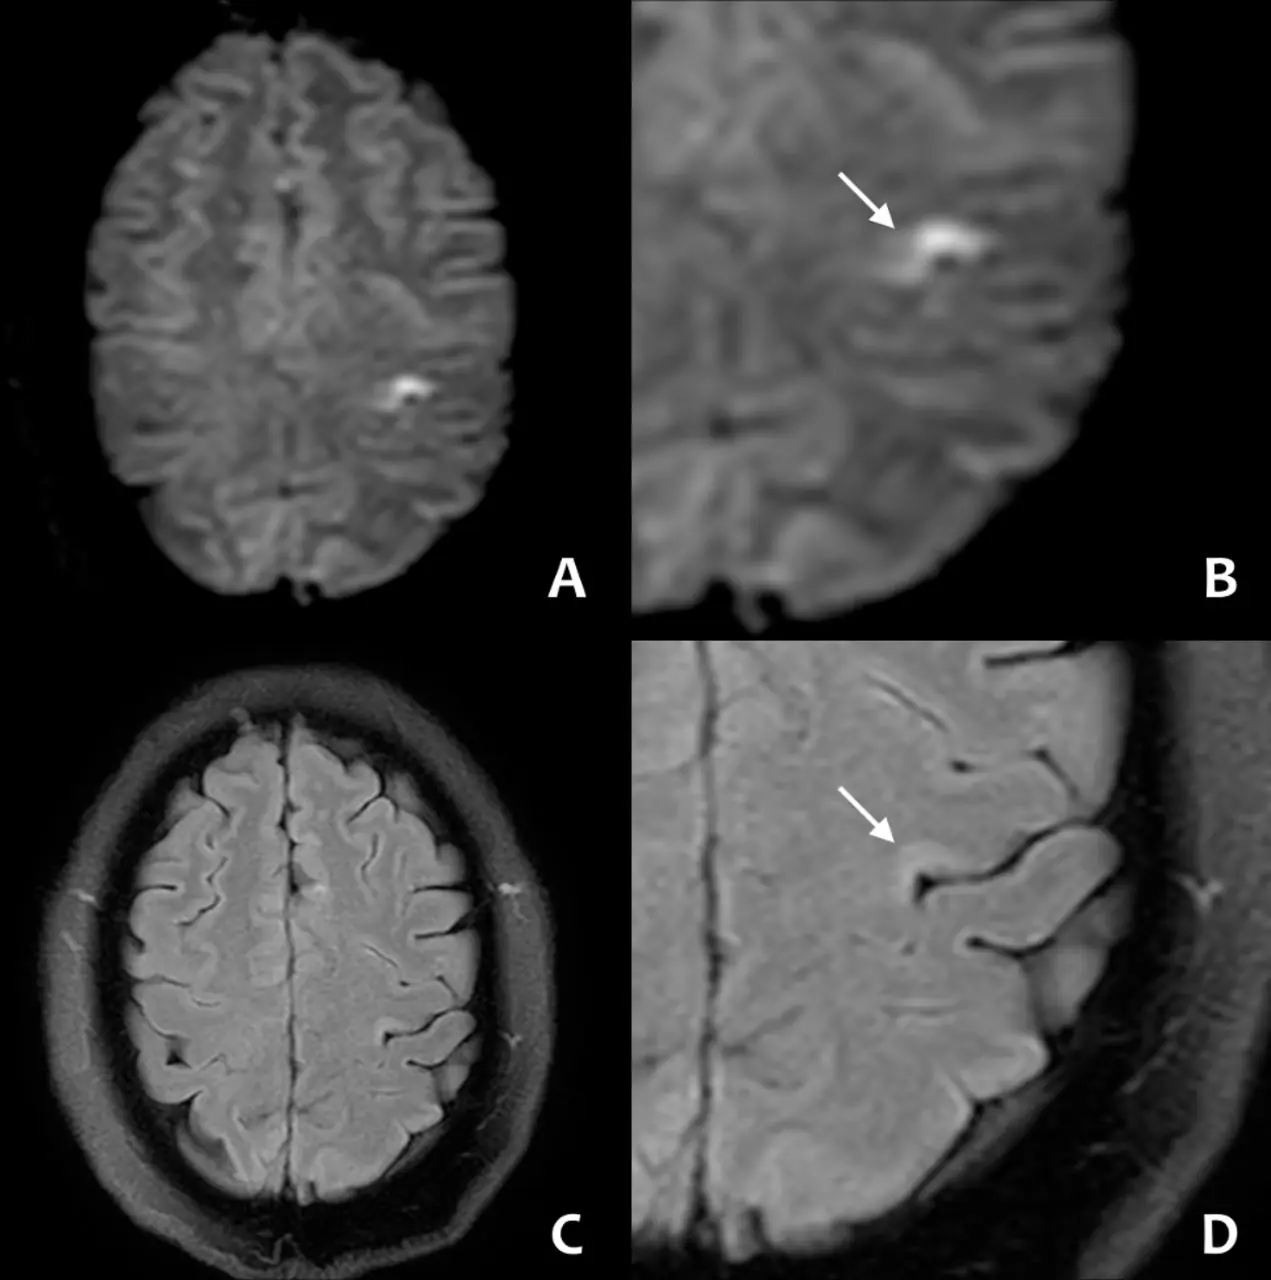

ปวดหัวอย่าชะล่าใจ อาจเป็นสัญญาณโรคร้าย เสี่ยงสโตรกในคนอายุน้อย